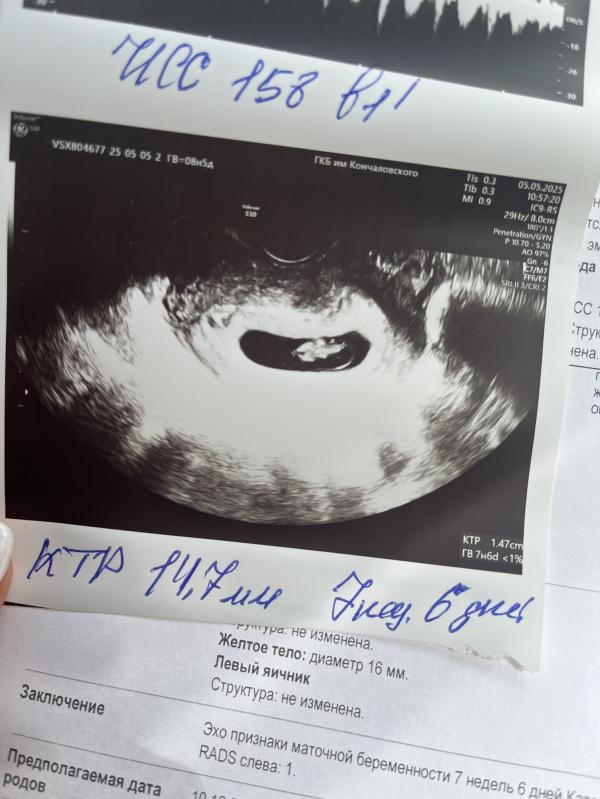

05.05.25г мы были на УЗИ как и назначил нам врач.

Установили правильный срок (рознился по дате последней менструации на 1 неделю и пару дней). Сердцебиение эмбриона в норме, размер соответствует сроку.